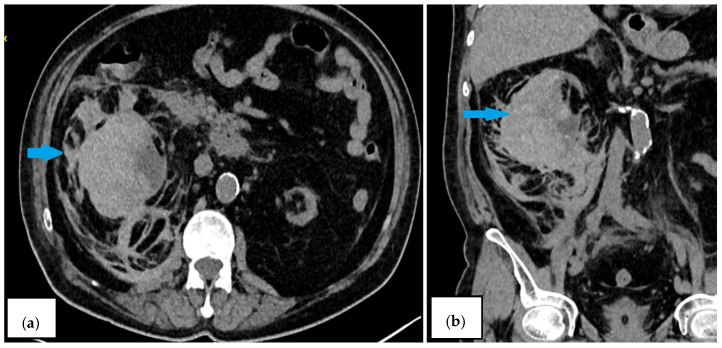

Background and Clinical Significance: Spontaneous renal hematoma, also known as Wunderlich syndrome (WS), is a rare disease characterized by the acute onset of spontaneous renal hemorrhage into the subcapsular, perirenal, and/or pararenal spaces without a history of prior trauma. WS can be a life-threatening condition due to hemorrhagic shock; consequently, prompt diagnosis and a therapeutic approach are essential for favorable outcomes. Treatment ranges from conservative management to surgical intervention. The most common etiologies are neoplasms and vascular diseases, but WS can also be observed in patients undergoing hemodialysis. In patients with end-stage renal disease (ESRD), especially those on hemodialysis, acquired cystic kidney disease and renal cell carcinoma are among the primary causes of WS. Although less common, WS can develop in dialysis patients even in the absence of traditional (primary) risk factors. In general, patients with chronic kidney disease (CKD) have a paradoxical hemostatic profile, likely explaining their higher tendency to bleed, so WS can occur without existing predisposing factors. The multifactorial pathogenesis in these patients includes functional platelet abnormalities, intimal arterial fibrosis, chronic inflammation, and oxidative stress associated with ESRD. The use of hemodialysis-related antithrombotic medications could serve as another contributing factor increasing the risk of bleeding. Case Presentation: We present a case report of a 62-year-old male on chronic dialysis who developed sudden right-sided lumbar pain and hematuria during dialysis without evidence of prior trauma. Imaging revealed a large subcapsular hematoma of the right kidney. Further investigations did not reveal additional risk factors in this instance; however, his routinely used hemodialysis-related antithrombotic medications were potentially a contributing factor. Despite conservative treatment, his condition worsened, and the hematoma enlarged, requiring emergency nephrectomy. Postoperatively, his condition gradually improved. Conclusions: This case highlights the importance of considering WS in hemodialysis patients, even without the presence of traditional risk factors, as well as including WS in the differential diagnosis of acute abdominal pain.